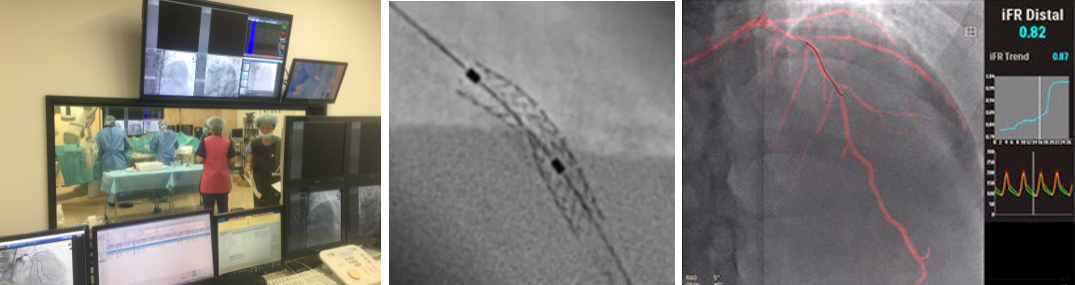

これまで、CTでは評価が難しいとされている冠動脈の強い石灰化部位やステント治療部位において、我々が考案した特殊な撮影(test bolus tracking法)および画像処理技術を用いて評価可能な画像を可能な限り提供しています。

通常の画像(左)に比べ、石灰化(白い部分)を除去した画像(右)では血管狭窄の有無が明瞭に評価できます。

通常の画像(左)ではSTENT内の評価は困難ですが、サブトラクション画像(中央)によって末梢側に高度狭窄を疑われます(矢印)。カテーテル造影(右)でも同様の位置に高度狭窄病変を認めます(矢印)。

Yamaguchi T. Ichikawa K, Takahashi D. et.al. A New Contrast Enhancement Protocol for Subtraction Coronary Computed Tomography Requiring a Short Breath-Holding Time. Academic Radiology Published online: October 17, 2016